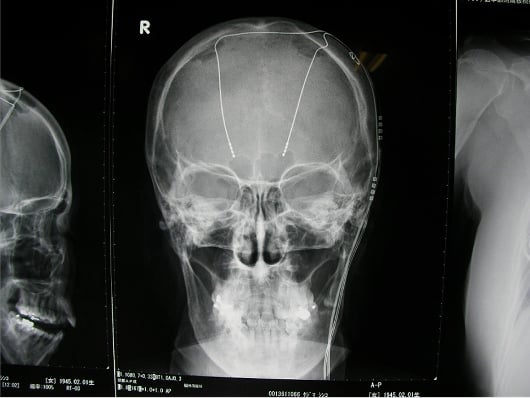

パーキンソン病、本態性振戦をはじめとする不随意運動疾患を対象に行われる脳深部刺激療法(DBS)(図参照)では、術後、一部の症例でうつ状態やアパシーといった精神障害や認知機能障害を呈することが明らかにされていますが、その機序について十分に解明されていません。本研究は北大病院の自主臨床研究として(自014-0032)、DBS後の高次脳機能について各種臨床心理検査と機能画像を用いて前向きに調査し、高次脳機能変化と特定の脳領域の活動変化との関連について解明することを目的としています。